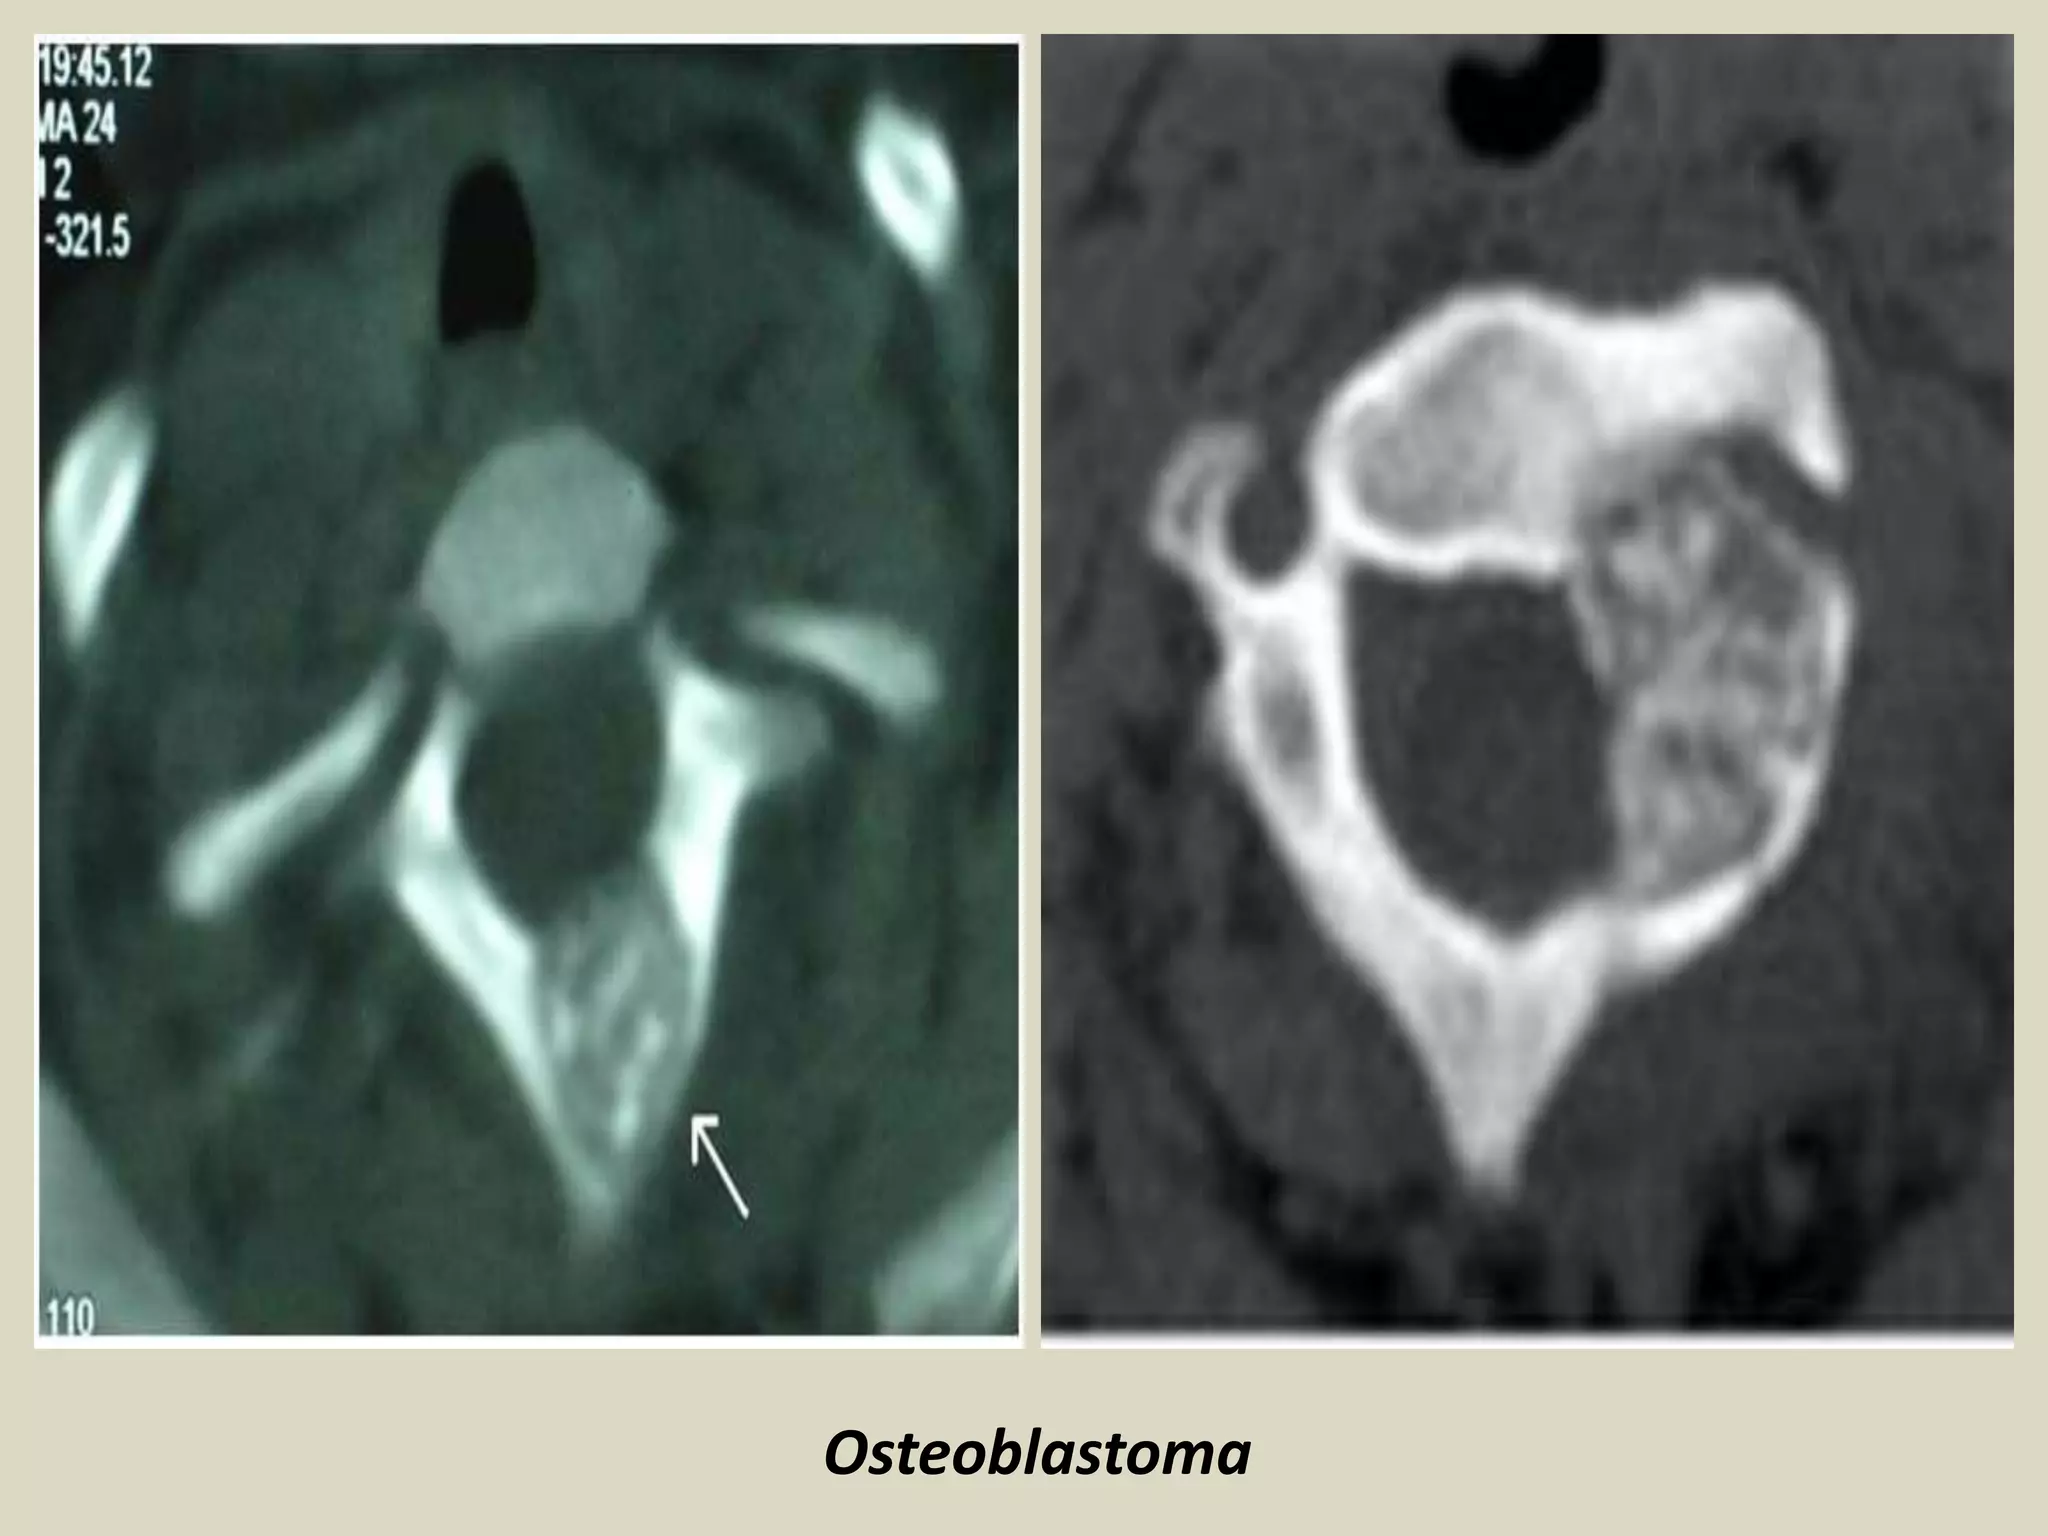

Osteoblastoma

Osteoblastoma.

Imaging:

- Lytic well circumscribed oval or round defect

-Almost always confined by a periosteal shell of reactive bone.